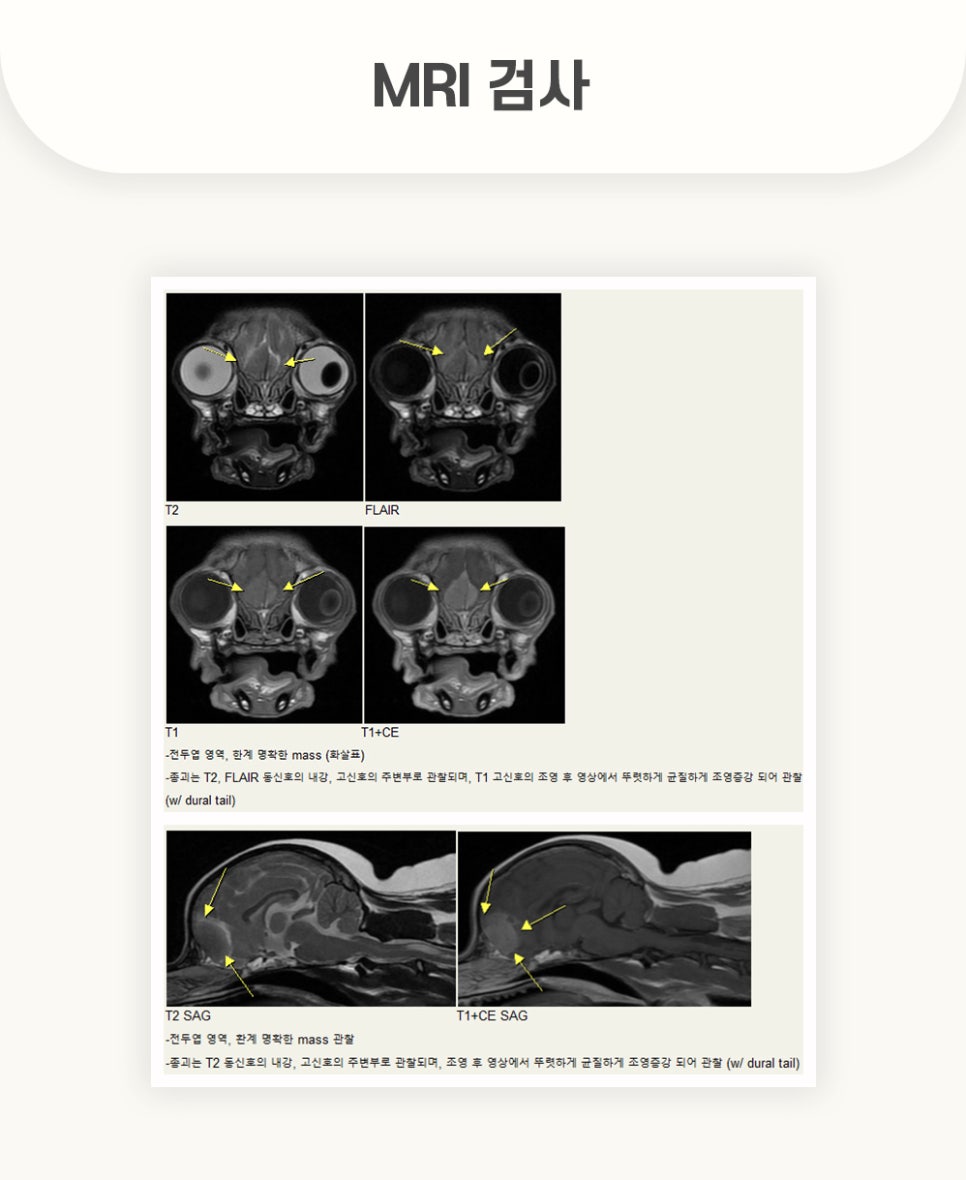

우선적으로 실행한 MRI 촬영 결과, 검사 화면에서 강아지 뇌 종양을 확인할 수 있었습니다.

전두엽 측 뇌수막종과, 원인 불명의 뇌수막염, 후두골 이형성 등이 관찰되었습니다.